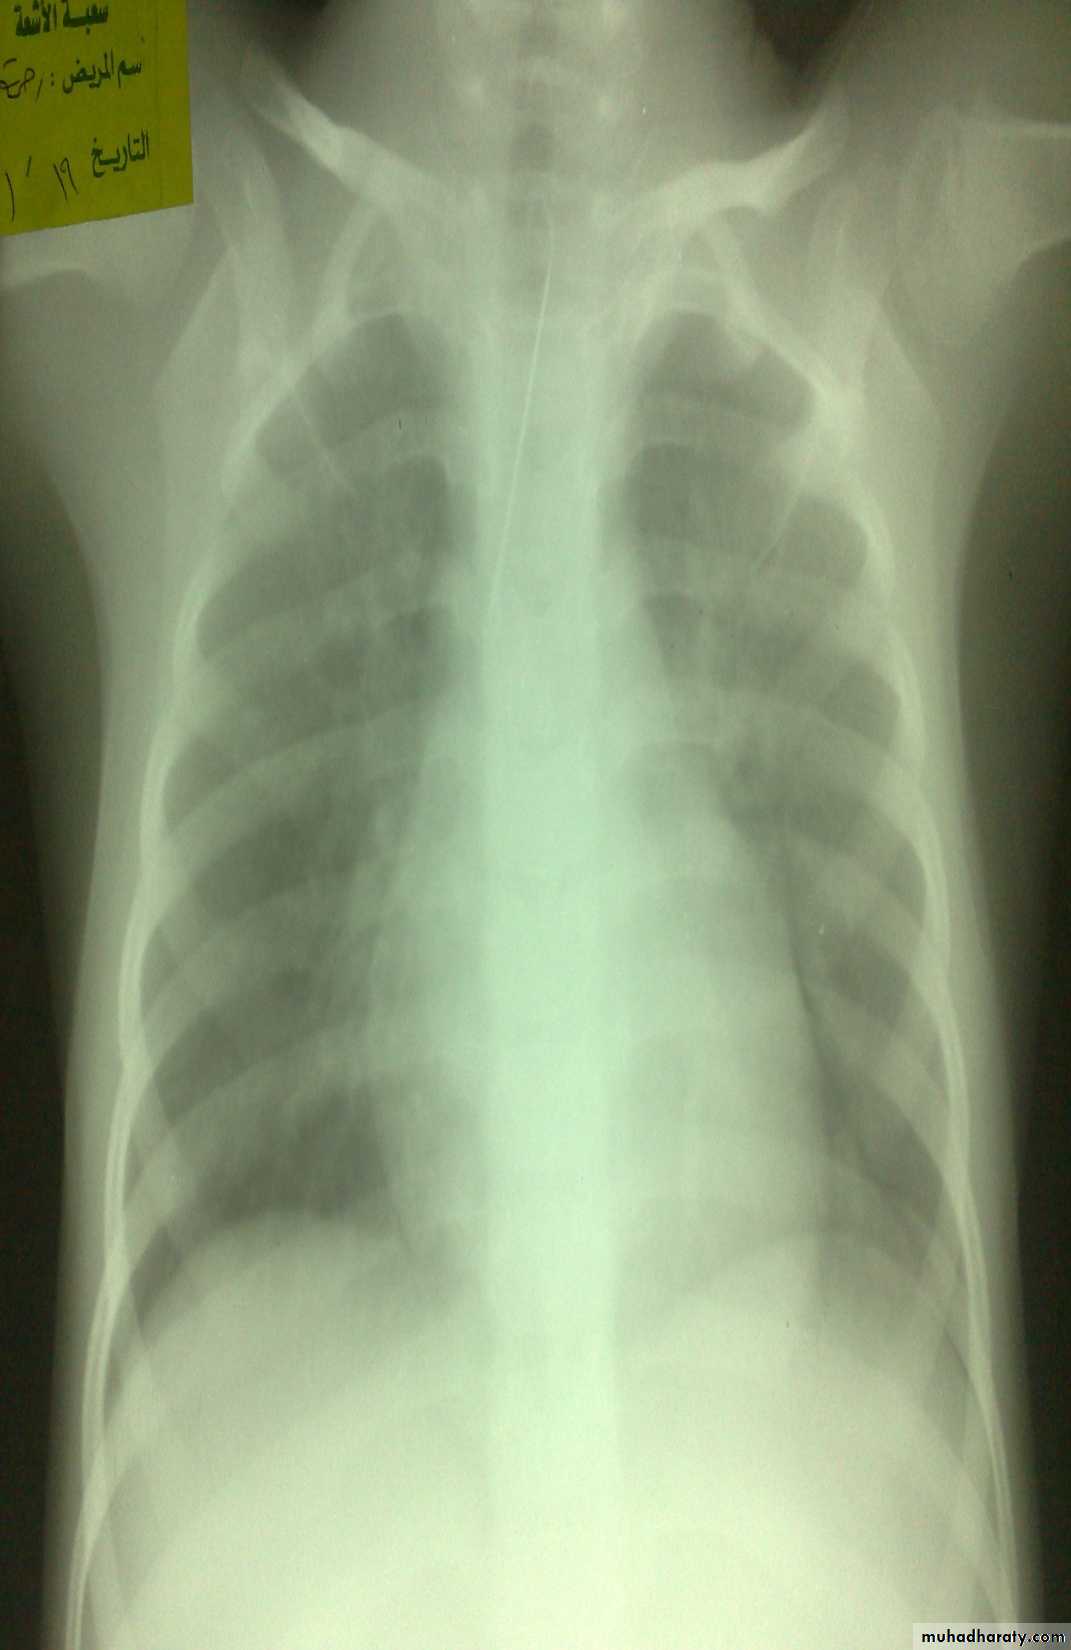

• Chest infection

Ba-swallow dilatation of esophagus with narrowing of lower part.